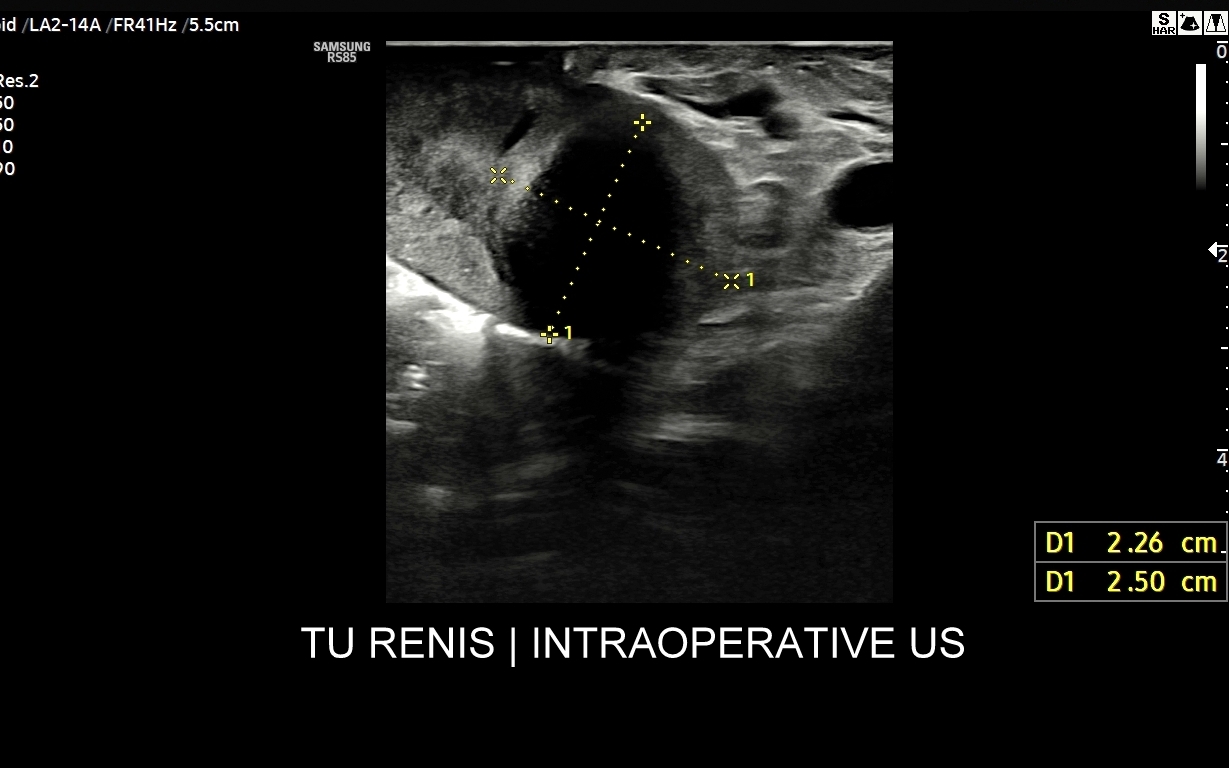

Badanie USG z kontrastem, nazywane również CEUS (ang. contrast enhenced ultrasound), jest nowoczesną metodą diagnostyczną wykorzystywaną w różnorodnych wskazaniach medycznych, w szczególności przy ocenie guzów i zmian ogniskowych narządów wewnętrznych takich jak wątroba, nerki, trzustka, drogi żółciowe, naczynia krwionośne, a także piersi i jądra. Badanie CEUS wykonają Państwo w Interdyscyplinarnej Pracowni Ultrasonograficznej prowadzonej przez dr Tomasza Szczepańskiego we Wrocławiu, pioniera ambulatoryjnych oraz szpitalnych zastosowań badań CEUS w Polsce.

Badanie USG z kontrastem, z języka angielskiego CEUS (contrast enhanced ultrasound), jest badaniem ultrasonograficznym, podczas którego, zwykle dożylnie, podaje się specjalny kontrast w celu uwidocznienia struktur narządowych oraz tkanek, które niewystarczająco wyraźnie są widoczne lub charakteryzowane w klasycznym badaniu USG, a nawet w innych badaniach obrazowych jak tomografia komputerowa (TK) czy rezonans magnetyczny (MRI).

Narządem, w którego diagnostyce najczęściej wykorzystuje się CEUS, jest wątroba; w dalszej kolejności nerki, trzustka, protezy naczyniowe aorty, drogi żółciowe oraz inne narządy wewnętrzne.